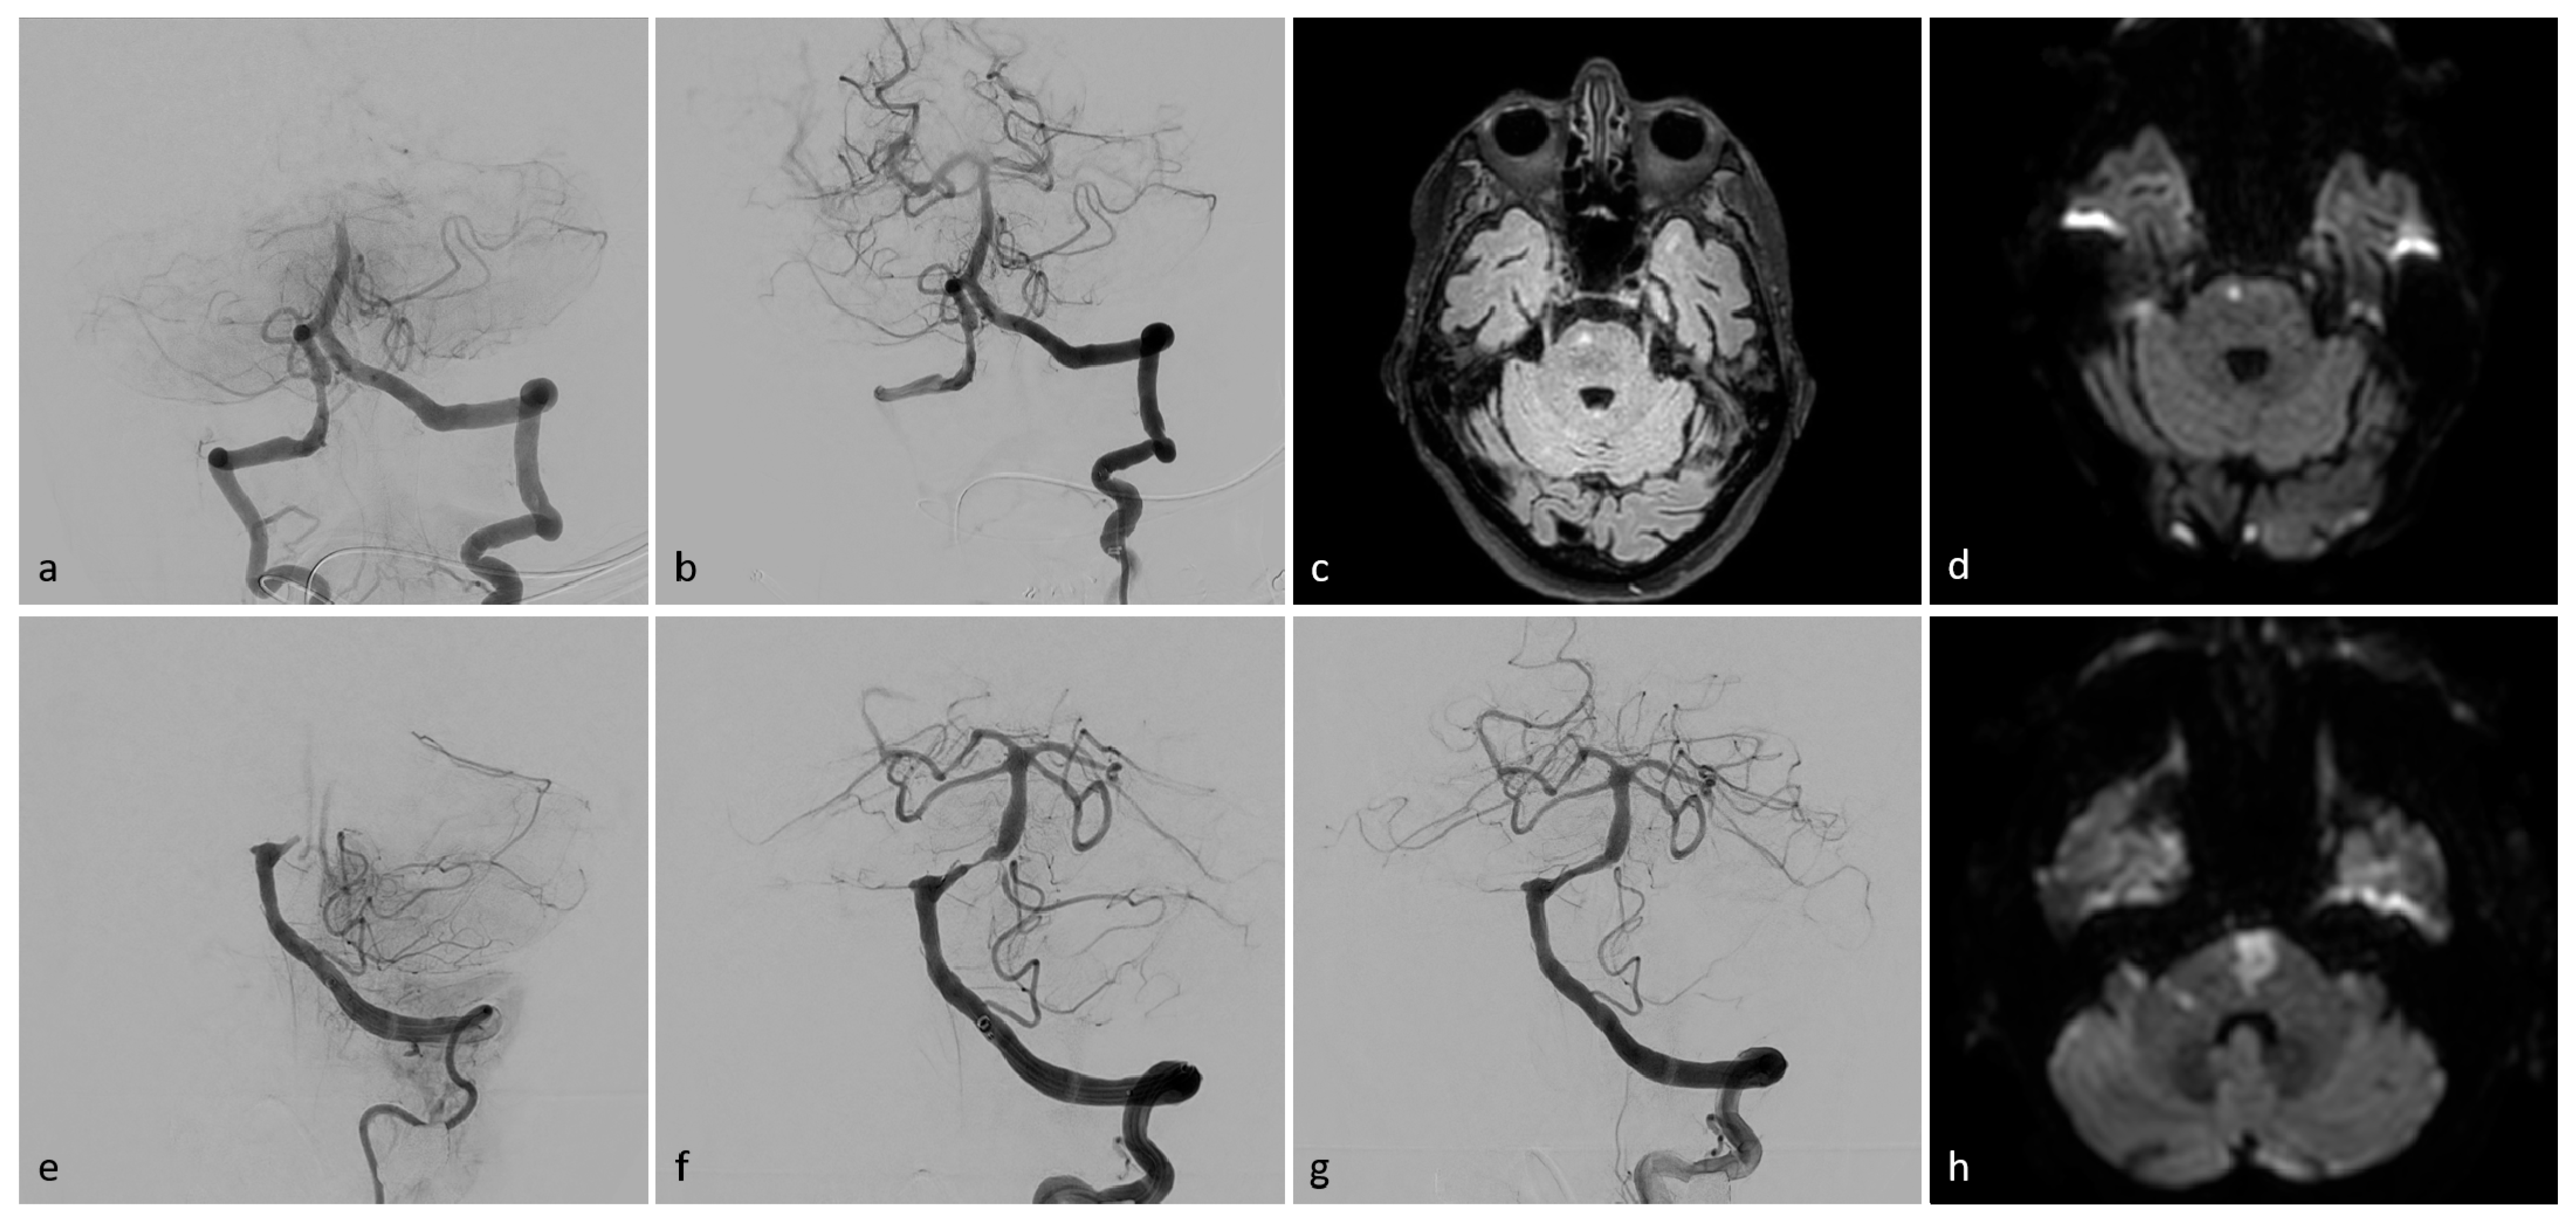

Figure 2.

Exemplary patient imaging. Intraprocedural angiographic images (a,b,e–g), fluid-attenuated inversion recovery (FLAIR), magnetic resonance imaging (MRI, (c)), and diffusion-weighted images (DWI, (d,h)). Patient I (a–d): A 73-year-old man presented with left-sided weakness and vertigo, followed by a coma. Initial angiography revealed occlusion of the basilar head (a). Successful TICI 3 recanalization was achieved after a single aspiration thrombectomy (b). MR-imaging showed a small paramedian pontine infarct on the right side (c,d). The patient was discharged with mild left-sided hemiparesis (mRS 2). Patient II (e–h): A 78-year-old woman presented with acute-onset tetraplegia. Initial angiography (e) showed proximal occlusion of the basilar artery. Post-thrombectomy, high-grade stenosis was observed in the proximal third of the basilar artery (f). After percutaneous transluminal angioplasty (PTA) and stenting, the stenosis resolved, with a final result of TICI 3 (g). DW imaging revealed an infarct in the pons and a small infarct in the right cerebellar peduncle (h). The patient was discharged with persistent tetraparesis, unable to walk without assistance (mRS 4).